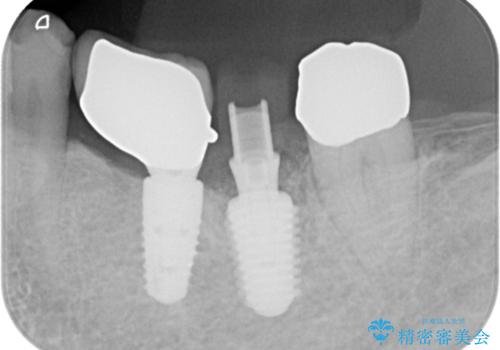

歯の保存は困難と診断しインプラントで治療を行いました。1Dayインプラントの適応だったので、抜歯した当日にインプラントを埋入しました。

1Dayインプラントは低侵襲なので痛みもほとんどありません。従来のインプラント治療だと1年弱かかるのが、3ヵ月で治療を終える事が出来ました。

1Dayインプラントとは抜歯と同時にインプラントを埋入する治療です。

従来のインプラント治療よりも低侵襲かつ短期間で治療を終える事が出来ます。